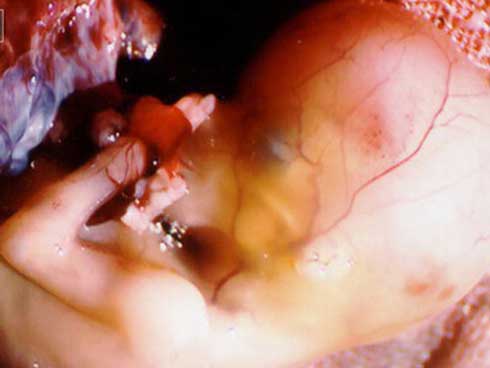

Bác sĩ đã lấy ra gần 2 lít máu máu loãng và máu cục, đồng thời tiến hành cắt tử cung hoàn toàn. Sau gần 2 giờ tập trung phẫu thuật, sản phụ và cháu sơ sinh đã qua giai đoạn nguy hiểm.

Theo bác sĩ Hùng đây là một trường hợp tai biến sản khoa nguy hiểm và hiếm gặp. Nếu không được cấp cứu điều trị kịp thời thì cả thai nhi và thai phụ đều có nguy cơ tử vong .

Bác sĩ Hùng cho biết khi hỏi người nhà bệnh nhân thì họ nói sản phụ không chủ động đẻ tại nhà mà do gọi xe đến bệnh viện không kịp sau đó xảy ra tai biến vỡ tử cung. Khi vào viện phẫu thuật xong, bác sĩ cũng phải truyền bù lại hơn 1 lít máu cho sản phụ.

Bác sĩ Hùng cho biết tai biến vỡ tử cung có thể xảy ra ở bất cứ sản phụ nào, nếu sản phụ có vết mổ sinh trước thì nguy cơ vỡ tử cung còn tăng gấp 5, 6 lần và không thể dự phòng được nguy cơ vỡ tử cung. May mắn cho sản phụ trên là tới bệnh viện kịp thời.